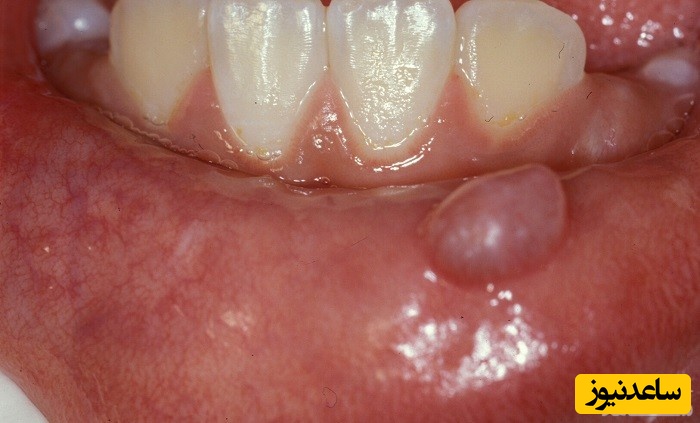

موکوسل تورم پر از مایع در لب یا داخل دهان است که می تواند هم دردناک و هم نازیبا باشد. جمع شدن مخاط در داخل یک کیست برآمده که در این ناحیه از دهان ظاهر می شود، موکوسل نام دارد. موکوسل ها قاعدتا دردی ندارند و معمولا پس از یک آسیب کوچک مانند بریدگی یا شکاف بر روی این ناحیه از دهان به وجود می آیند. موکوسل ها به طور معمول نیازی به درمان ندارند و ممکن است خودشان از بین بروند اما اگر شخصی دارای موکوسل خیلی بزرگی است و یا مرتب بروز می کند، دندانپزشک بدون هیچ خطری، می تواند آن را خارج کند.